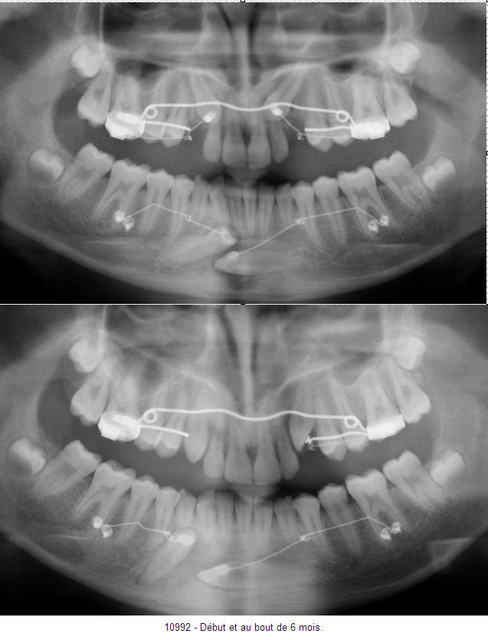

Pano du haut : 11 mai 2007

Pano du bas : 02 novembre 2007.

J'ai viré la 83 et changé la direction de la traction du fil baliste pour faire effectuer maintenant un mouvement vertical à la 43.

La 33 ne s'est pas encore déplacé, je vais augmenter l'activation de la "canne à pêche" et surtout changer l'orientation de la traction pour un mouvement vers le haut, maintenant que la couronne de 43 a laissé la place.

A l'arcade supérieure, pas de problème, c'est plus banal.